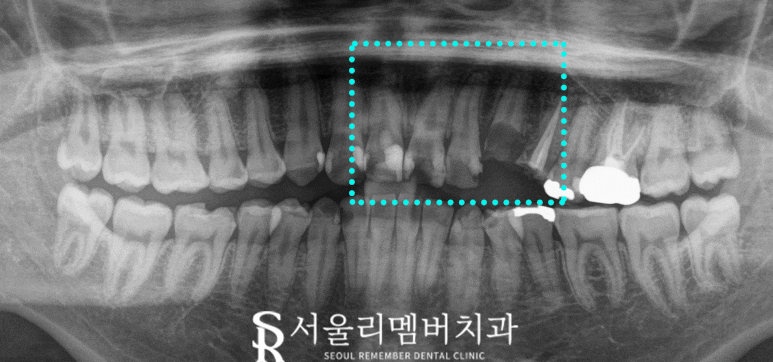

전후 사진으로 보여 드리겠습니다.

x-ray를 먼저 보겠습니다.

부러지고 충치로 가득 차 있던 앞니는 보존하고

그리고 임플란트 식립한 부위는

튼튼한 치아들을 관찰할 수 있습니다.